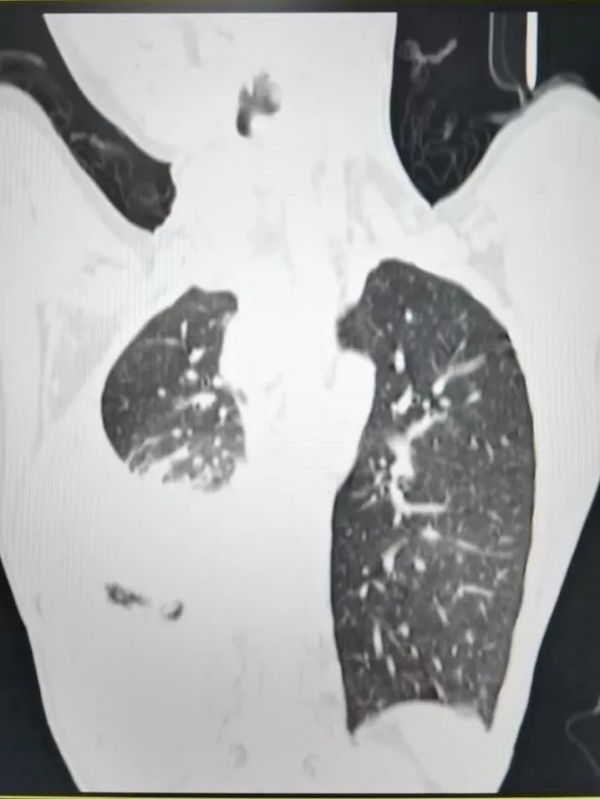

10岁患儿,体重仅40多斤,严重营养不良,身体消瘦,确诊结核时右肺多处纤维化,右肺功能部分丧失

“每个人的症状其实都不一样,大多数肺结核患儿并没有明显的咳嗽,但几乎都有消瘦。结核是消耗性的慢性疾病。”黄丽素表示,在判断是不是结核病的时候,不能根据是否有猛烈咳嗽来简单判断,而应该结合病人是否有明确的结核接触史来综合考虑。这个孩子全身明显消瘦、营养不良,其实这也是肺结核典型症状之一。